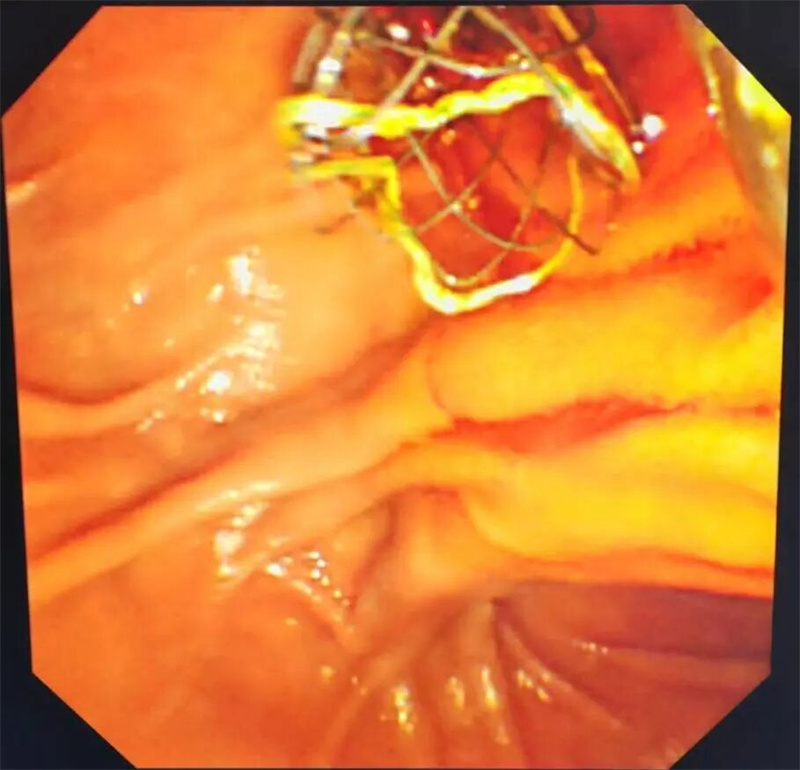

通过检查,于蕾发现患者胆管末端存在占位性病变伴胰管重度扩张,明确诊断为梗阻性黄疸。

手术于9月4日进行。术中,肝胆外科副主任医师王福刚通过将内镜从患者创口进入直到十二指肠,在胆管开口处精确植入金属支架,将原来堵塞的“运输桥梁”再次支撑起来,使淤积的胆汁能够顺利通畅流出;麻醉科主任王志茹则全程在手术室密切检测患者生命体征变化。在手术团队的协助下,整个手术仅用时25分钟就顺利结束。